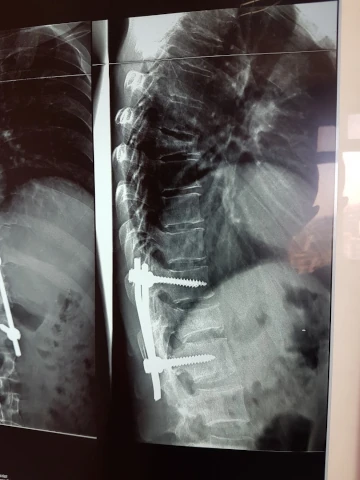

Galerie